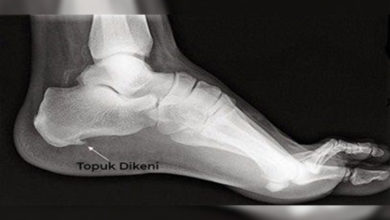

topuk dikeni

Topuk Dikeni nedir? Nedenleri ve Günlük hayatınızı kolaylaştıracak öneriler

Uzun süre ayakta durmak Topuk dikeni sebebi

Topuk Dikeni Cilt Sorunları ile Karıştırılabiliyor